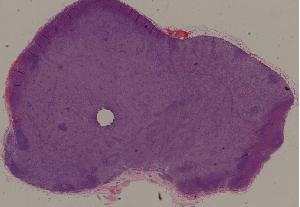

36.恶性淋巴瘤